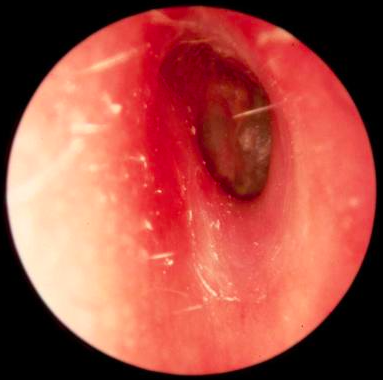

1. Otoscopia

1. Piel de conducto macerada, inflamación, abundante secreción restos epiteliales, disminución calibre.